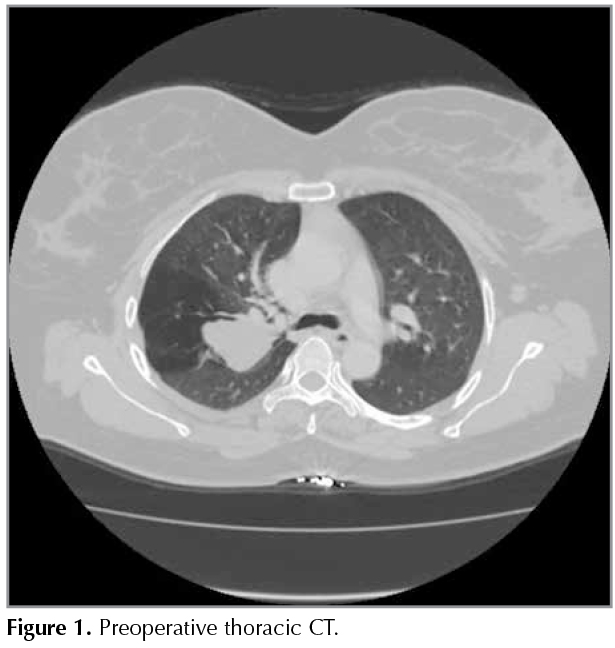

A 40-year-old female patient presented to the polyclinic with complaints of coughing and shortness of breath that were present in the past two months, but exacerbated further in severity in the past week. The physical examination showed more pronounced rhoncus in the right side. The patient had received treatment for non-specific infections at other centers. Furthermore, the results of positron emission tomography/computer-assisted tomography (PET-CT) obtained by reason of the request of another centre were compiled in a report which indicated the absence of pathologic uptake. Thoracic CT resulted in the observation of a 3 x 3 x 5 cm low-density mass lesion adjacent to the major fissure in the posterior segment of the upper lobe of the right lung with no indication of the bronchus of the same lobar segment and the indication of trapped air in the periphery of the lesion (Figure 1). Fiberoptic bronchoscopy (FOB) showed that the inlet mucosa in the posterior segment of the right upper lobe had been narrowed down due to external pressure and all other lobar and segmental inlets were open. The patient was diagnosed radiologically and clinically with atresia in the posterior segment of the upper lobe of the right lung. As the patient's complaints did not recede despite bronchodilator therapy, the thoracic surgery department was consulted and the patient underwent an operation. The operation removed fluid-filled cystic lesion and the pathological examination indicated it to be lung tissue featuring emphysematous changes. Post-operative thoracic CT indicated smaller dimensions for the low-density mass when compared to that in the pre-operative phase (Figure 2). The patient has been on follow-up at our polyclinic for the past two years and currently has no complaints.

Figure 1